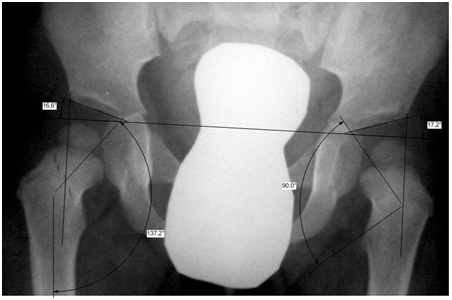

Рентген ТБС: Нормальные показатели

Раздел: Необычные решения